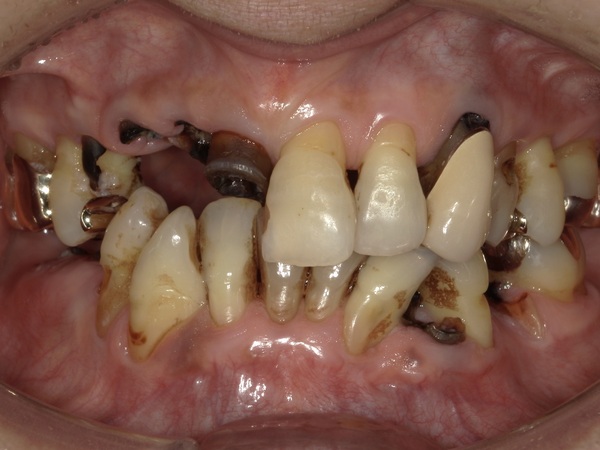

こちらが初診時のお口の中の写真となります。

右上の前歯の差し歯が取れてしまい、根っこだけが残ってしまっている状態です。

右下・左下にも同じように根っこだけの歯がいくつかあります。